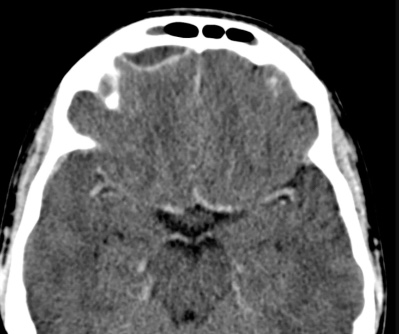

- Abcès lenticulaire

- Prise de contraste de la paroi

- Sinusite associée

- Pneumocéphalie